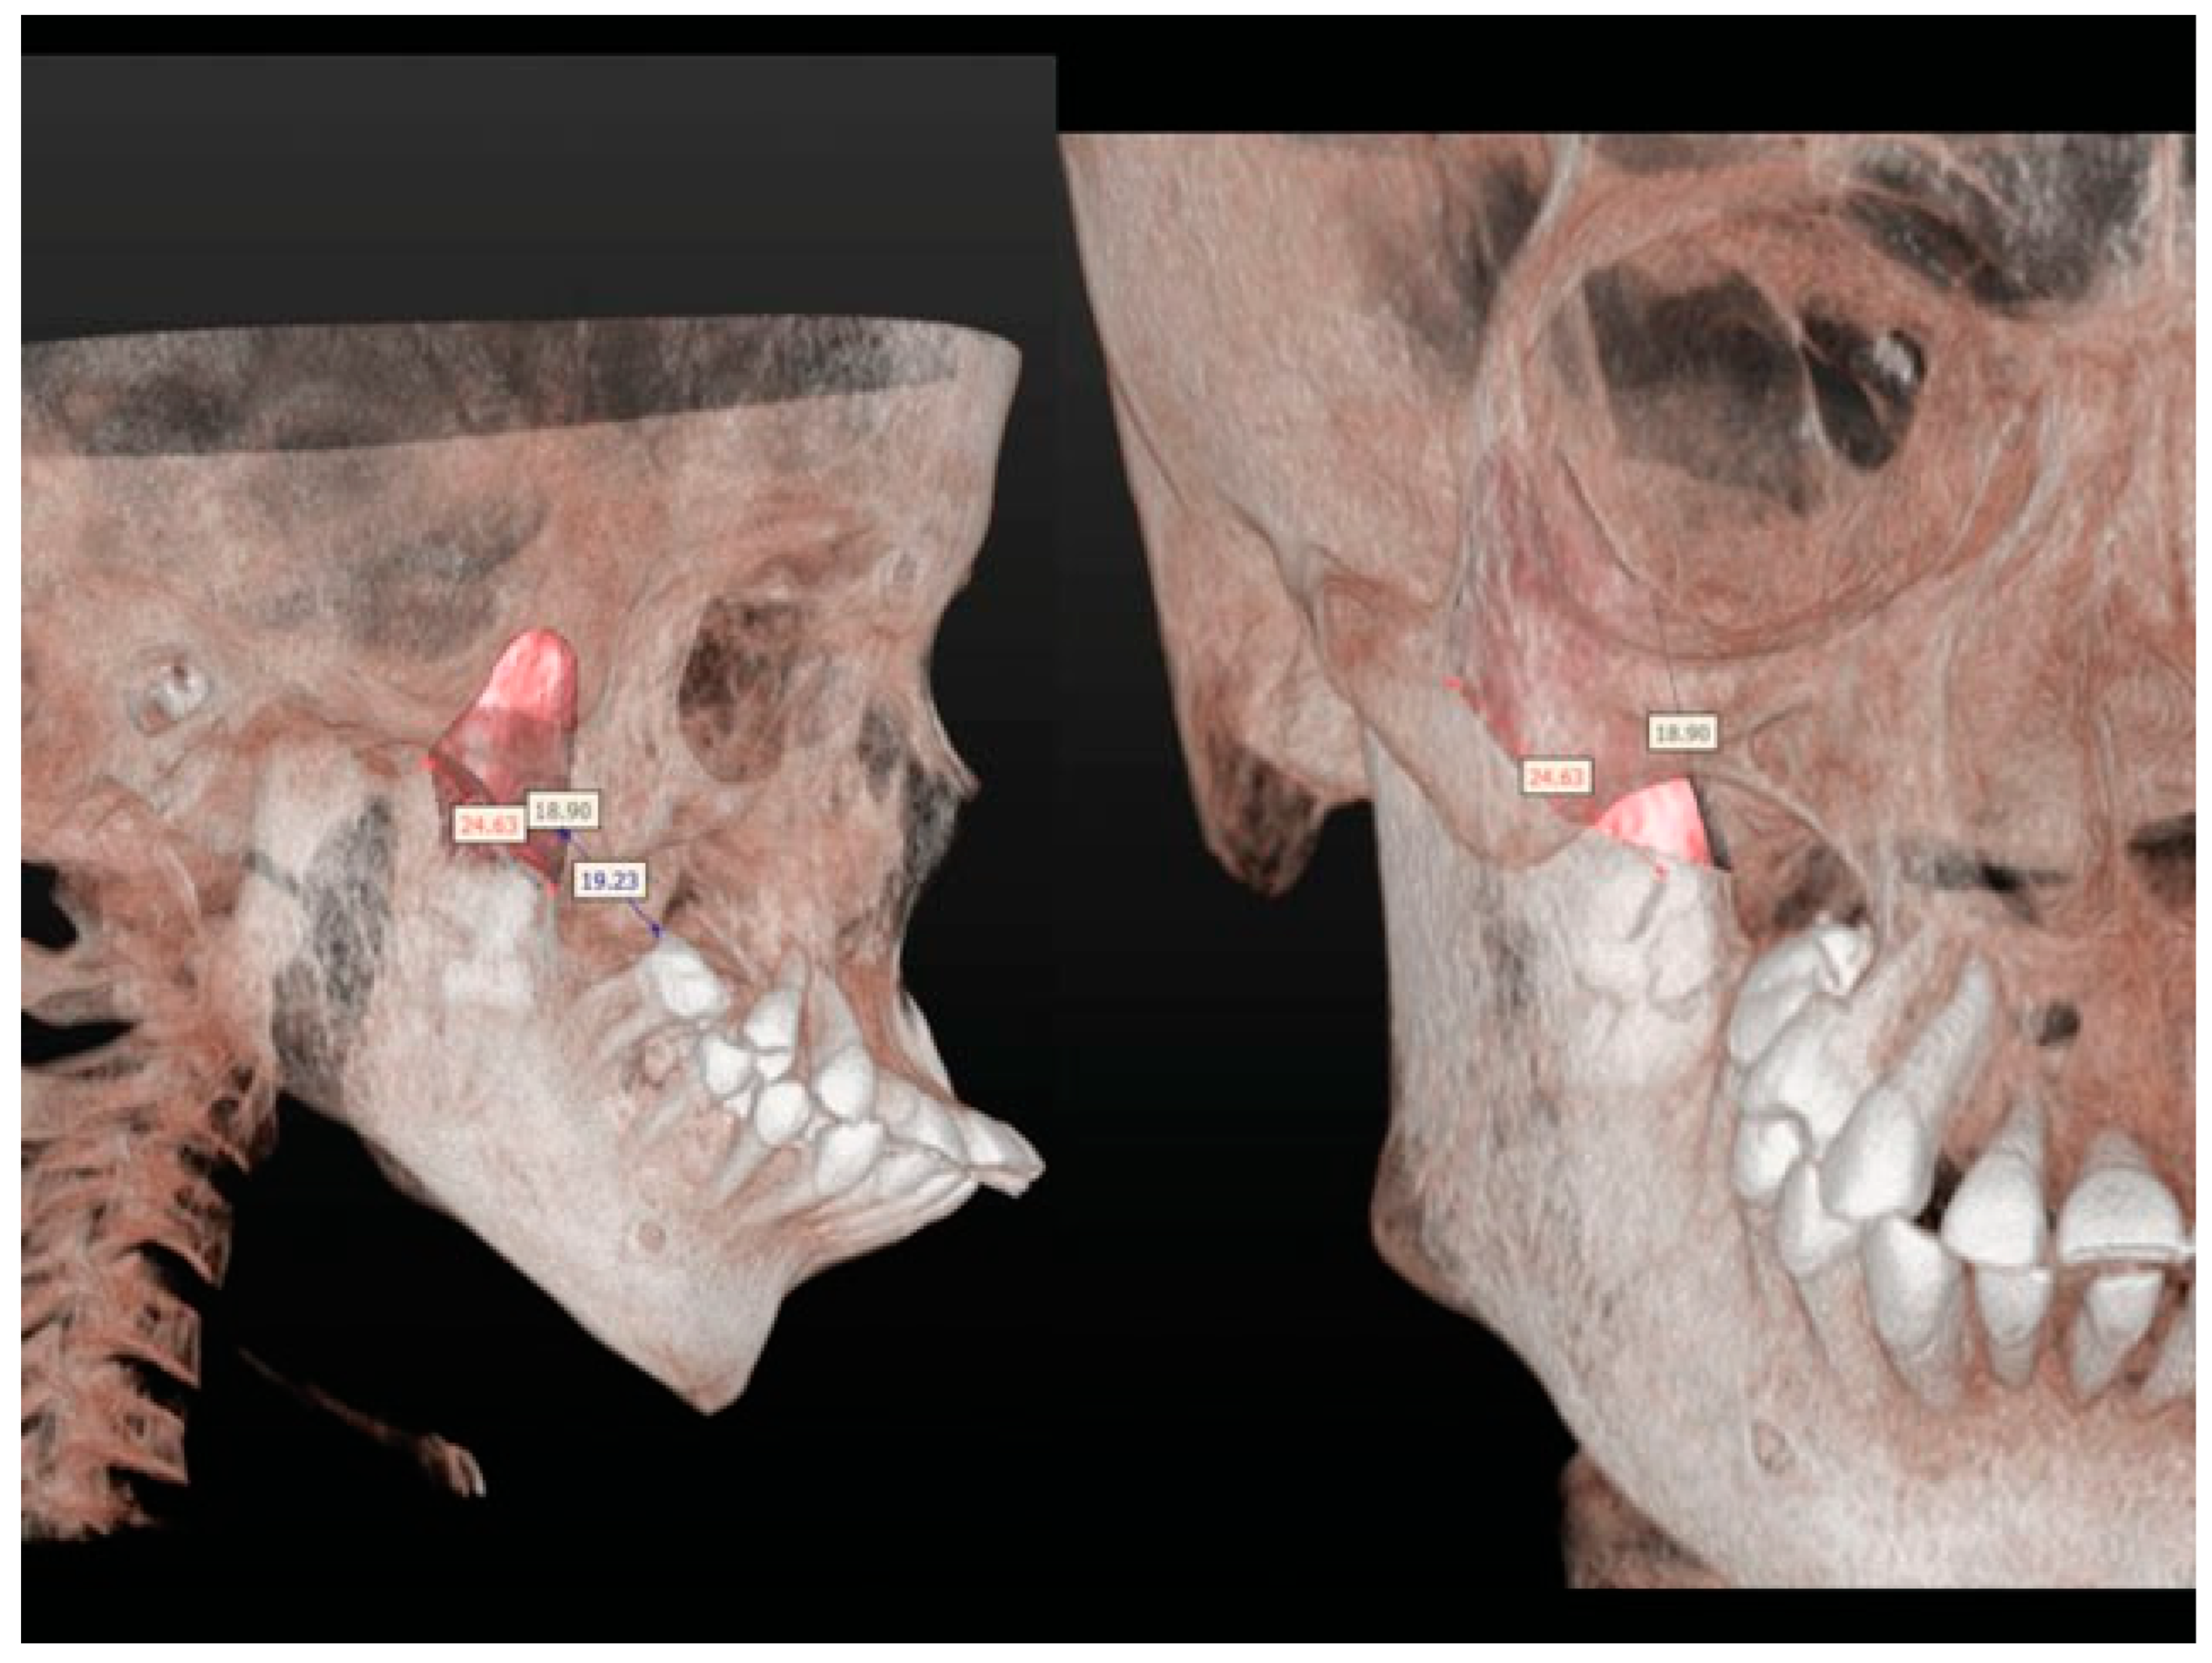

Figure 6. 3D planning of the surgery.

Figure 7. 3D planning of the surgery.

A facial angio-CT scan was performed to study cervical vascular anatomy and to discard anatomical variants at the level of the internal maxillary artery. Heteroanamnesis revealed a family history of endogamy and second-degree consanguinity. 3D planning of the surgery was performed with SimPlant O&O (Materialise Dental/Dentsply Implants, Mölndal, Sweden) to study the patient’s anatomy and design the necessary osteotomies to separate the jaws (Figure 6 and Figure 7). Thanks to the 3D preparation, the surgical access could be decided on an intraoral approach with sufficient exposure to do the osteotomy and ostectomy seemed feasible. In case the access was insufficient, a hemicoronal approach with osteotomy of the zygomatic arch had to be considered.